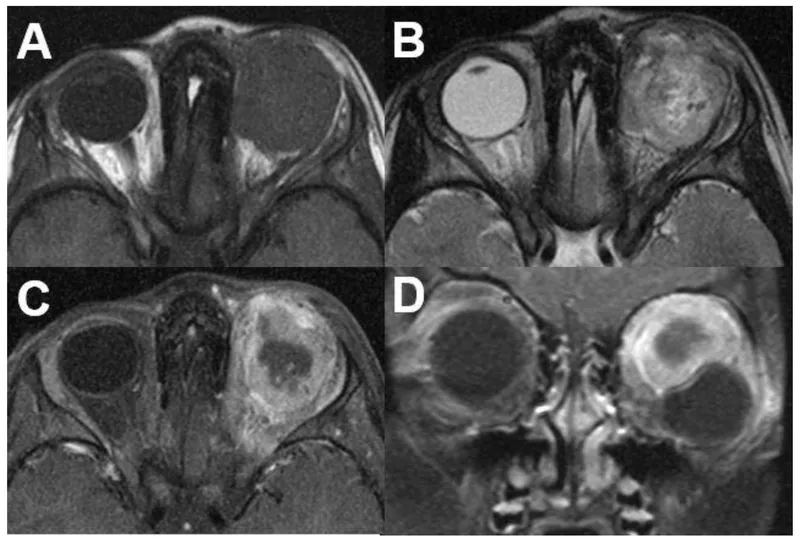

- CT: Preferred for bone destruction; shows mass, extent.

- MRI: Superior for soft tissue, perineural spread, intracranial extension.